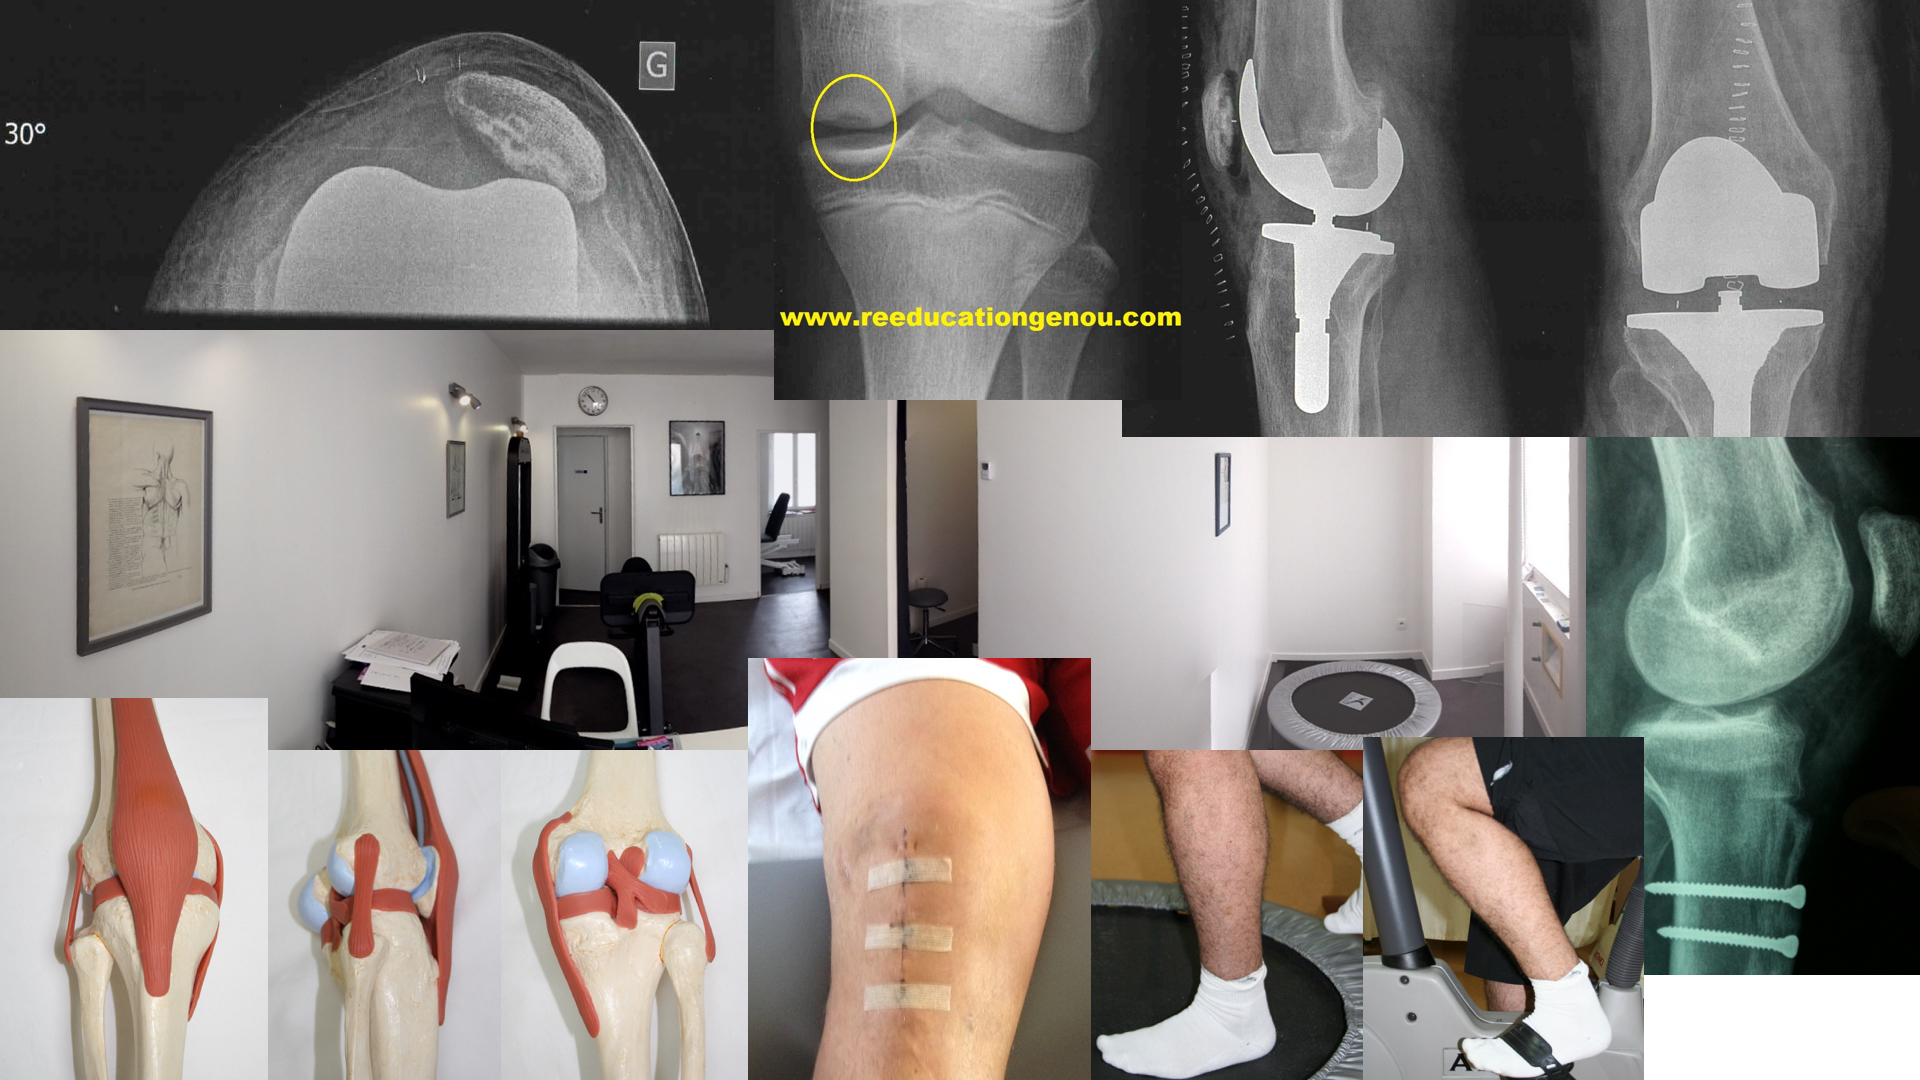

Sur cette page vous trouverez mes ouvrages de références et bibliographies dont je me sers au quotidien et comme livre de chevet pour ma pratique quotidienne et surtout pour ne pas raconter n'importe quoi....

La kinésithérapie n'a pas le même niveau de preuve concernant ses pratiques que la médecine ou les médicaments mais nos techniques tendent à être comparées pour devenir valides et donc non dangereuses.

Les publications suivantes valident donc nos pratiques manuelles et empiriques par des tests et analyses (et mieux encore des méta-analyses).

Les 316 bibliographies utilisées pour élaborer ce site : LCA, rotule, prothèse, ligaments, return to play or to sport, ménisques...

Les ouvrages de référence concernant le genou

Pathologie ligamentaire du genou (2004) : ouvrage majeur

650 pages !

La bible parue en 2004 pour toutes les nouveautés et les références sur les communications sur le genou ligamentaire de l'anatomie à la chirurgie jusqu'en 2003 inclus (P. LANDREAU, P. CHRISTEL, P. DJIAN)

My knee expérience (2006)

• fantastique ouvrage probablement destiné aux chirurgiens et aux mordus de genou comme moi... regroupant les 10 opérations les plus fréquentes en chirurgie du genou, pratiquées par l'équipe lyonnaise. génial !

Pathologie femoro patellaire...

ouvrage très ancien que l'on retrouve souvent dans les bibliographies